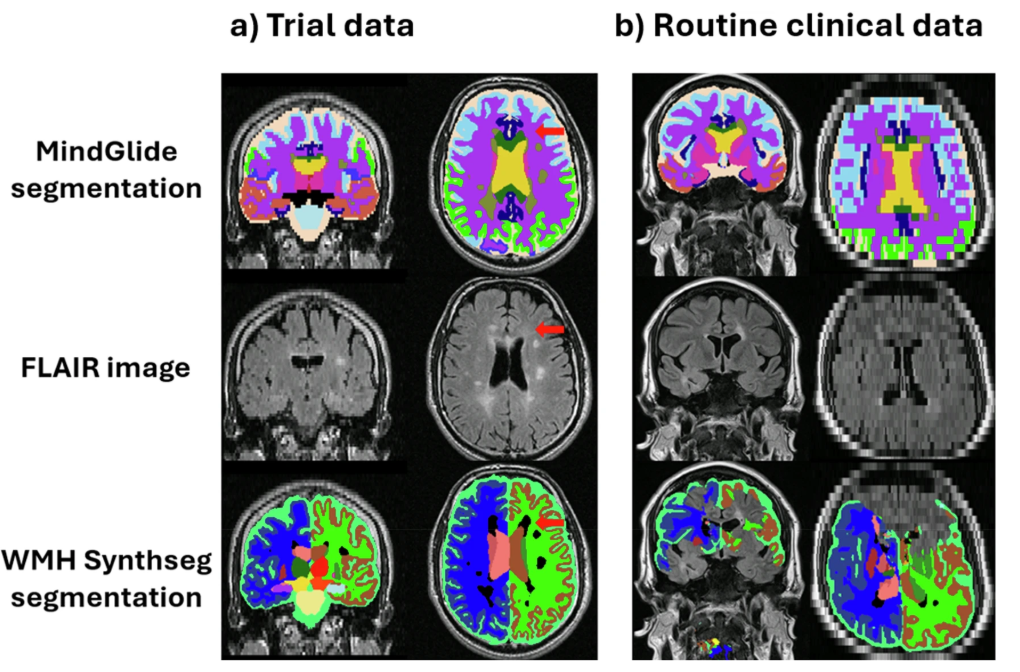

在检测脑组织损失的治疗效果中,MindGlide 显示了治疗组皮质 GM 体积损失率明显低于安慰剂组。下图为各种对比的分割示例。

另外在常规护理临床数据集中,研究人员目视检查了 WMH-Synthseg 和 MindGlide,结果显示,前者显示出显著的失败率,尤其是扫描厚度超过 5mm 时。在视觉评估的 433 个对比中,WMH-Synthseg 未能分割 65 个扫描,而 MindGlide 仅有 6 个。示例如下图。

MindGlide 和 WMH-Synthseg 分割示例

其中,图 (b) 显示了常规护理临床数据集 (RRMS) 中的一个厚度为 7mm 的切片,WMH-Synthseg 分割失败。这是因为大多数分割工具被设计为使用优劣采集方向,而 MindGlide 允许对任何方向获取的图像进行分割。